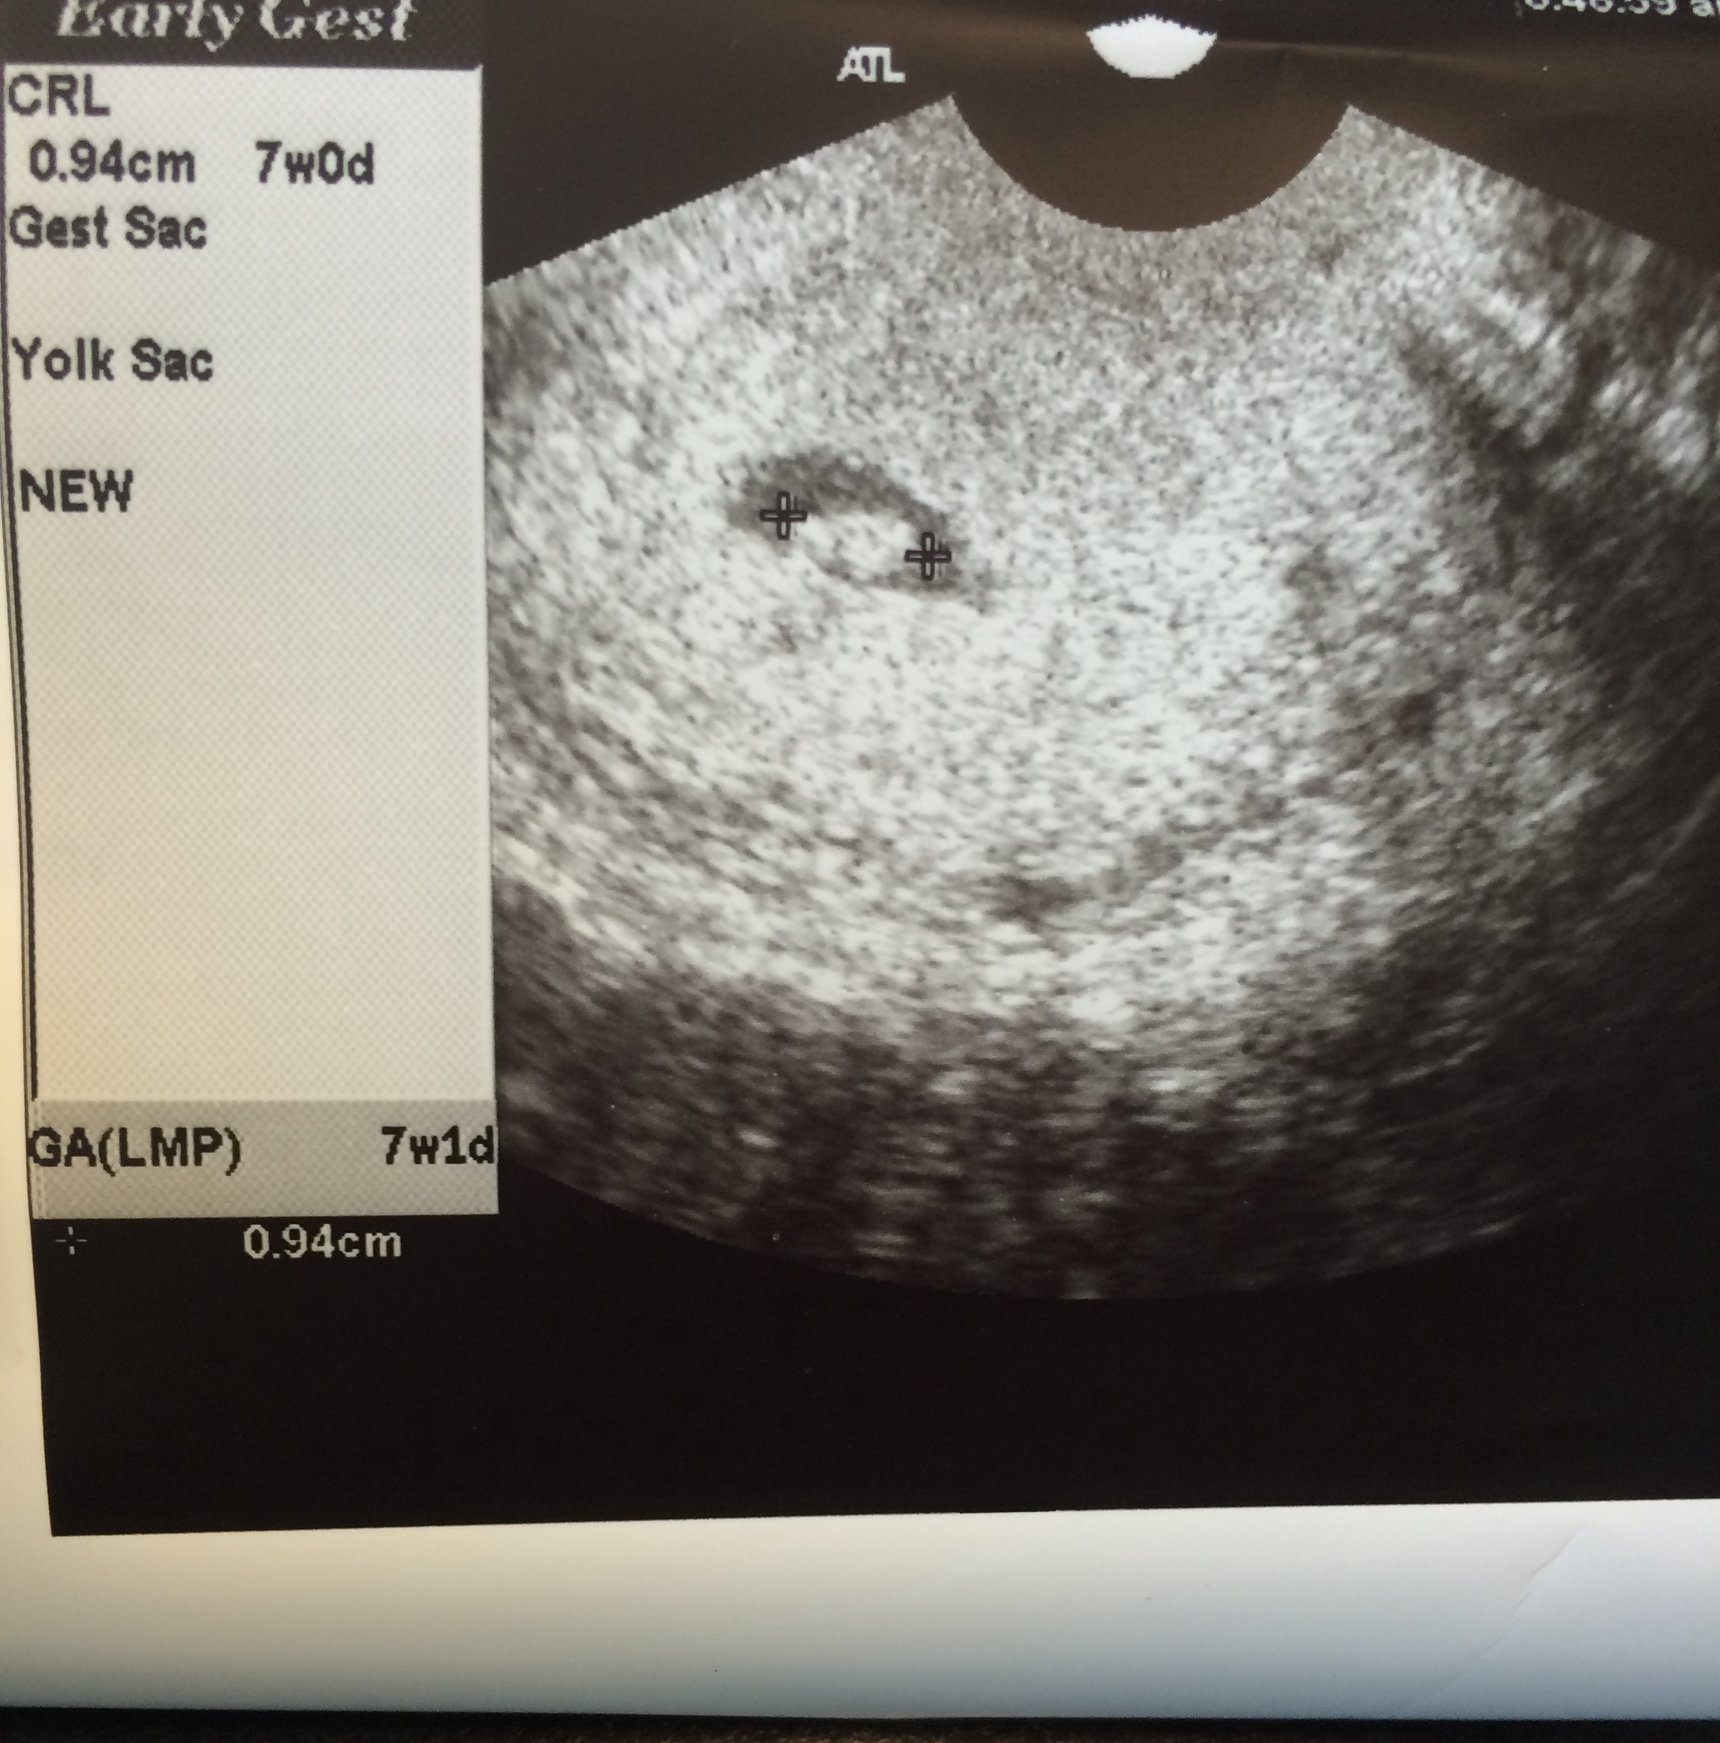

I still have the fear in the back of my mind (this ultrasound will be at 7w1d, and our first baby stopped growing at 7w1d), but I am still excited that things are looking good so far.

I got my test results today, my HCG level was 29,983. The doctor called me today to let me know that these results looked good and that my levels were progressing enough for her. Now I have my first ultrasound in 1 week! I'm so excited!